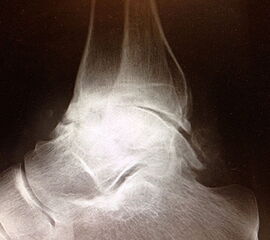

Kapsulotomie und Synovialektomie. Entknorpeln der Gelenkflächen bis knapp in den subchondralen Raum. Mit Kuretten, gebogenem Meißel, oszillierender Säge und/oder hochtourigen Fräsen Entknorpeln der tibialen, fibularen und tibialen Gelenkfläche und Abtragung von knöchernen Anbauten (Abb. 3). Die Präparation entlang der vorgegebenen Kontur des Talus und der Tibia bietet den Vorteil eines geringeren Längenverlustes gegenüber geraden Sägeschnitten. Der anteriore Zugang bietet insbesondere bei Verwendung eines Arthrodese Spreizers eine gute Übersicht in die anterioren Kompartimente. Der antero-laterale transfibuläre Zugang ergibt eine hervorragende Übersicht, allerdings nicht auf das mediale tibio-talare Kompatiment.

Anbohren der subchondralen Sklerosezone mit einem 2 bis 3,5 mm Bohrer zur Verbesserung der Durchblutung (Abb. 4).

Abbildung 3

Abbildung 4